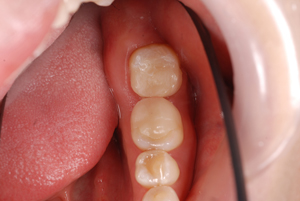

セット後

セット後![]() |

これで健康的な口元になり、大きく口を開けて笑った写真も気になりません。